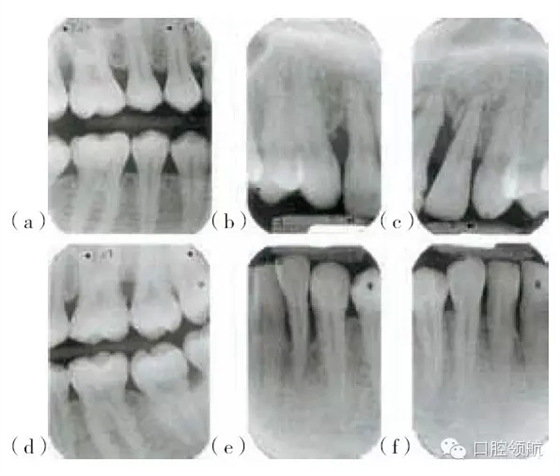

圖29.5 (a,d)圖29.4患者的X線片,咬合面的X線片顯示上頜第一磨牙遠中及下頜左側(cè)

第二磨牙,有齦下牙石和牙槽骨吸收。(b,c,e,f)根尖片顯示右上側(cè)切牙,左上中切

牙及側(cè)切牙,左下側(cè)切牙有齦下牙石及牙槽骨吸收